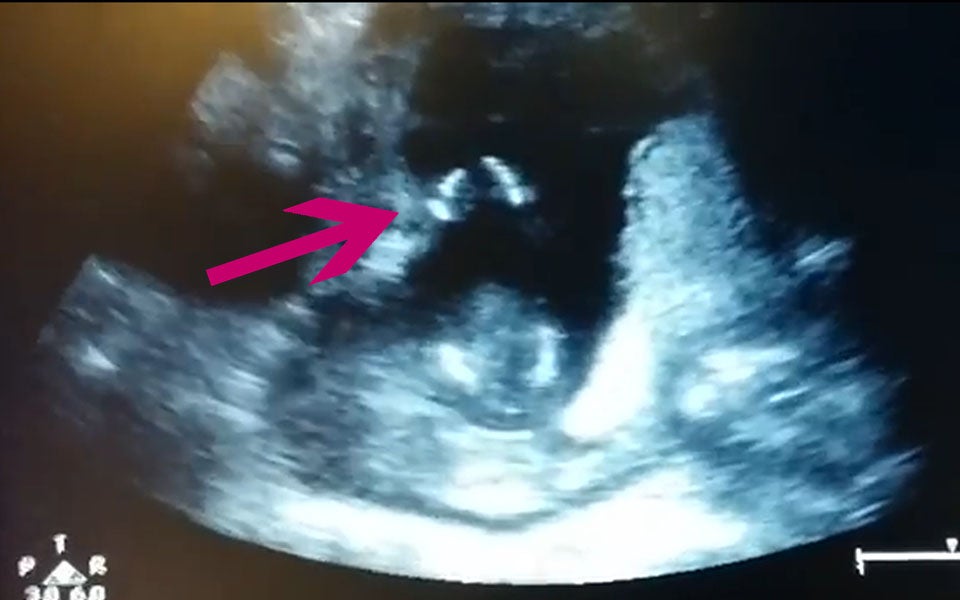

Dieser Fötus klatscht jetzt schon im Takt!

Als eine schwangere Frau und ihr Ehemann zum Frauenarzt gehen, um mal wieder eine Ultraschalluntersuchung zu machen, sehen sie etwas Unglaubliches: Ihr Baby klatscht in der Gebärmutter als wär es in einem Konzert! Spontan singen die werdenden Eltern „If you’re happy and you know it clap your hands..:“ (deutsch: Wenn du glücklich bist und es auch weißt, dann klatsche in die Hände…“)